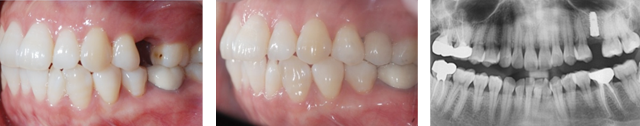

왼쪽 어금니 상실로 내원한 환자분. 위 턱뼈의 경우 아래턱뼈보다 얇고 상악동 있어 임플란트를 실패할 가능성이 높습니다. 턱뼈의 해부학적 구조를 충분히 고려한 상악동 뼈이식 후 임플란트를 식립하였습니다.